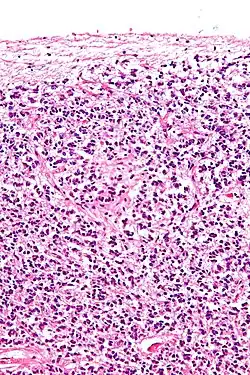

Los pinealocitos de Tipo 1 son también conocidos como los pinealocitos de la luz, ya que se tiñen a una densidad muy baja cuando se observan bajo la luz de un microscopio y aparecen más claros para el ojo humano. Estas células de Tipo 1 han sido identificadas por tener una forma oval o redonda y un diámetro que oscila entre los 7 y 11 micrómetros. Los pinealocitos de Tipo 1 suelen ser más numerosos tanto en niños como en adultos que los pinealocitos de Tipo 2. También están consideradas por ser las células más activas debido a la presencia de ciertos contenidos celulares, incluyendo una elevada concentración mitocondrial. Otro hallazgo consistente en los pinealocitos de Tipo 1 es el incremento en la tasa de lisosomas y gránulos densos presentes en las células conforme la edad del organismo se va incrementando, indicando posiblemente la importancia de la autofagocitosis en estas células. Investigaciones también han revelado que los pinealocitos de Tipo 1 contienen el neurotransmisor serotonina, que subsecuentemente es convertido en melatonina, la principal hormona secretada por la glándula pineal.

Los pinealocitos de Tipo 2, también conocidos como pinealocitos de la oscuridad, ya que se tiñen a una elevada densidad cuando se observan bajo la luz de un microscopio y aparecen más oscuros para el ojo humano. Como indican diversas investigaciones en microcopia, son células alargadas de forma oval o redonda con diámetro aproximado de entre 7 y 11.2 micrómetros. El núcleo de los pinealocitos de Tipo 2 contiene muchos repliegues que albergan grandes cantidades de ribosomas y de retículo endoplasmático rugoso. Una abundancia de cilios y de centriolos se han encontrado también en estas células de Tipo 2 de la glándula pineal. Solamente en el Tipo 2 está la presencia de vacuolas que alberga 2 capas de membrana. Como las células de Tipo 1 que contienen serotonina, las células de Tipo 2 albergan melatonina y se cree que tienen características similares a las células endocrinas y neuronales.